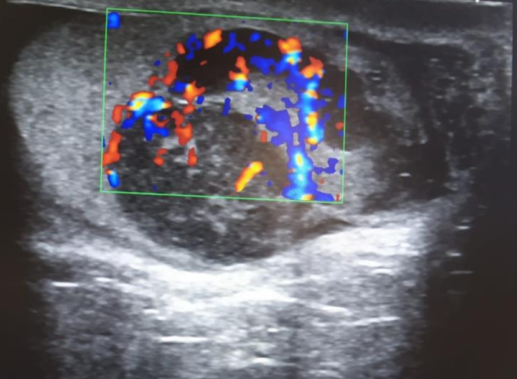

La ecografía (con doppler) informa de testículo derecho heterogéneo con múltiples áreas hipoecogénicas. Lesiones con marcada vascularización; compatibles con neoformación testicular derecha.